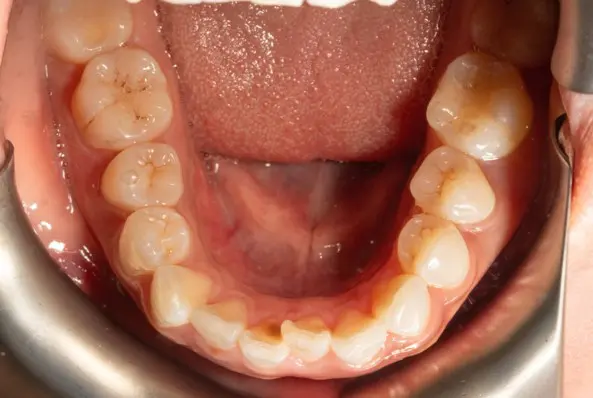

Crowding

Before

After